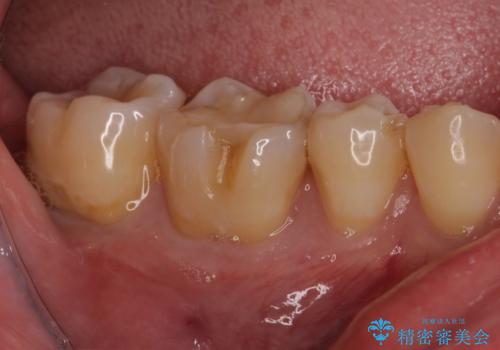

- 他院で行った、古いセラミックが欠けたとのことでご来院された患者様です。

古いセラミックを外すと、無数のヒビが入っており、そこからできた新しい虫歯がありました。

古い材料も虫歯もすべて除去して、根本からやりかえました。